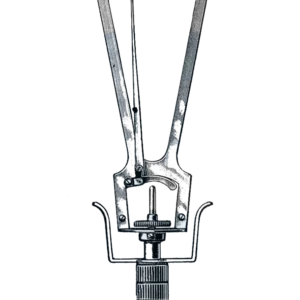

Ginekologiniai instrumentai (98)

Ginekologiniai skėtikliai (13)

Ginekologiniai instrumentai (98)

Ginekologiniai skėtikliai (13)